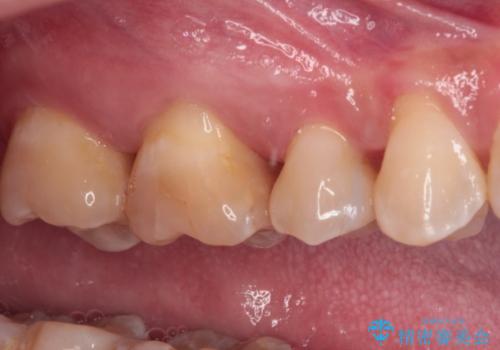

治療後は物が挟まることもなく、フロスが引っかかったり出血したりすることが減りました。